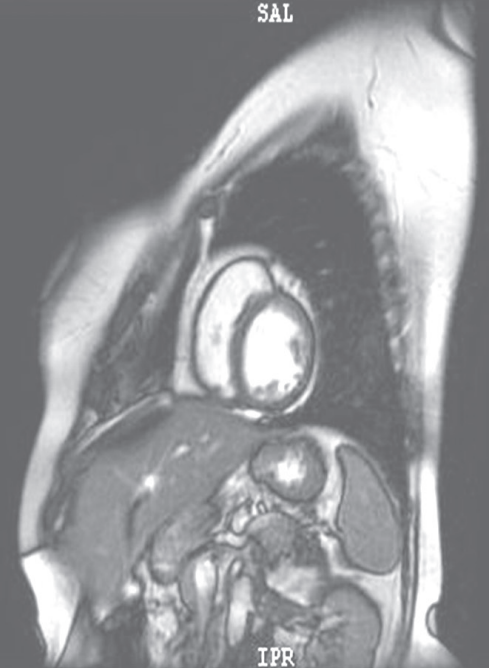

摘要:關(guān)于擴張性心肌病的最新治療,小巷深處的隱藏寶藏正逐漸為人們所發(fā)現(xiàn)。通過先進的醫(yī)療技術(shù)和方法,擴張性心肌病的治療取得了新的進展。這些治療方法旨在改善心臟功能,提高患者生活質(zhì)量。小巷深處的醫(yī)療機構(gòu)或?qū)<铱赡茈[藏著寶貴的治療經(jīng)驗和方法,為尋求最佳治療方案的病患帶來希望。更多詳細信息需要進一步探索和研究。

擴張性心肌病是一種嚴重的心臟疾病,但“心之港灣”為你帶來希望,這里的專家團隊一直在深入研究擴張性心肌病的最新治療方法,并深知每位患者都渴望得到最佳的治療和關(guān)懷,他們努力不懈,為患者帶來生機和新生。

你將了解到最新的藥物治療、心臟康復(fù)計劃以及生活方式調(diào)整等方面的知識?!靶闹蹫场边€開展了一系列臨床試驗,為患者提供最新的治療方案,他們的治療方法全面且個性化,因為每個患者的狀況都是獨特的,所以需要因人而異定制治療方案。